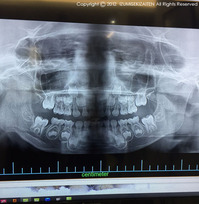

現場が好き 2019.01.24 屋根がかかった新しいおうちに、大工さんが常駐しいよいよ本格的な木工事が始まりました。朝の8時 続きを見る ドローン撮影 2019.01.23 棟上げの日は大一番。沢山の大工さんが一堂に会し、見た目が凄い早さで一番変化する日でもあります 続きを見る 姉妹、初の歯医者 2019.01.22 次女の3歳児健診で歯科検診を受けた際、極めて怪しい歯があるとのことで、姉妹は初めて歯医者さん 続きを見る 快気祝い 2019.01.21 流行に乗った次女との5日間の自宅軟禁生活は、もちろん1日中家で夫も長女は夫の実家に避難中で不 続きを見る ゼリーの幸せ再び5 2019.01.20 次女のインフルエンザが完治した頃、ちょっとした気分転換が届きました。過去に何度もこのブログに 続きを見る 上棟 2019.01.19 この日はとうとう上棟となりました。あいにく仕事が重なっていまして、半日ほど作業を見学して撤収 続きを見る 棟上げへ向けて 2019.01.18 ようやく木工事がスタートしました。プレカットの関係でちょっと工期が遅れましたが、何とか工事の 続きを見る 次女、流行に乗る 2019.01.17 次女の登園が始まって3日目の降園時に、これまでニコニコ登園して園内でも大人しく過ごしていた次 続きを見る カングーの法定点検 2019.01.16 先日カングーの法定点検がありました。ディーラーへクルマを預けている間、展示してあった新型アル 続きを見る 久々のトヨタ博物館その2 2019.01.15 写真はジャガーEタイプの内装。元々ジャガーEタイプは廉価なスポーツカーという位置づけ。それで 続きを見る 久々のトヨタ博物館その1 2019.01.14 娘と仕事をしに行った日は同時にカングーの法定点検でした。そこで法定点検の待ち時間に長女とトヨ 続きを見る 助手 2019.01.13 先日八事霊園に仕事で行ってきました。実は次女がインフルエンザになってしまいまして、暫く長女と 続きを見る 新年会 2019.01.12 本年初の新年会が先日我が家で行われました。大人子供合わせて8名の小さな宴会でしたが、この位の 続きを見る 次女、幼稚園に行く 2019.01.11 長女の通う幼稚園は、満3歳になると登園することができます。母としては春の本格的な入園まで待つ 続きを見る 帰省終了 2019.01.10 帰省を終える直前、何か足りないという気分の中で母の病院でふと気づいたのが、実家へ寄っていない 続きを見る LED化 2019.01.09 最近郵便局のカブをじっくり拝見する機会がありました。どうやら最新型のカブにはLEDヘッドライ 続きを見る ロミオとジュリエット 2019.01.08 入院中の実家の母が、リハビリが必要な状況となり、リハビリを専門とする病院への転院が完了しまし 続きを見る 播州の台北 2019.01.07 歴史を感じる看板には台北の文字が躍ります。普通なら本格的な台北の味を出して来ると思うでしょう 続きを見る てんしん 2019.01.06 義理の母がリハビリの為に明石の病院に入院していまして、その近くに明石焼きの美味い店があるとの 続きを見る 峰山高原 2019.01.05 兵庫県の神河町にある峰山高原に行って来ました。昨年夏に一度行っていまして、日本で14年ぶりの 続きを見る «←130131132133134→»